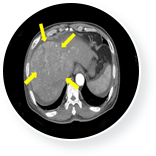

61세 남성 간암 환자는 간 내 다발성 종양 및 복수로 인해 수술이 불가능한 상태였습니다. 또한 간 혈관 변화로 인해 간암 치료 역시 불가능한 상태였습니다.

이때 3개월 간 매주 1회 일정으로 총 12회의 면역세포 치료를 실시하였고, 간암의 종양표 지자인 AFP가 치료 전 19,175(ng/ml)에서 치료 후 170(ng/ml)로 떨어졌습니다.

또한 CT검사 결과 간암의 축소 및 복수 소실이 확인되었습니다.

• 간암 치료 전 이미지

간암 치료 전